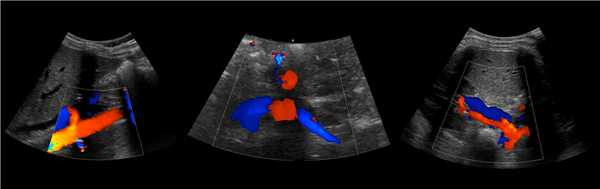

Рисунок. В режиме ЦДК на продольном (1) и поперечном (2) срезах от аорты отходят ППА и ЛПА. Сосуды направляются к воротам почки. Кпереди от почечной артерии располагается почечная вена (3).

Рисунок. Почечные вены впадают в нижнюю полую вену (1, 2). Аортомезентериальный «пинцет» может сдавливать ЛПВ (3).